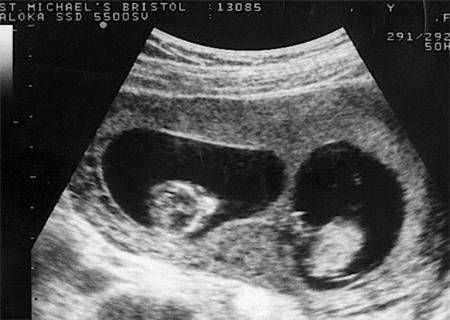

双胞胎流产图片大全

双胞胎流产图片大全,

深圳女子怀孕5次均流产第6次意外怀了双胞胎产检时医生却说